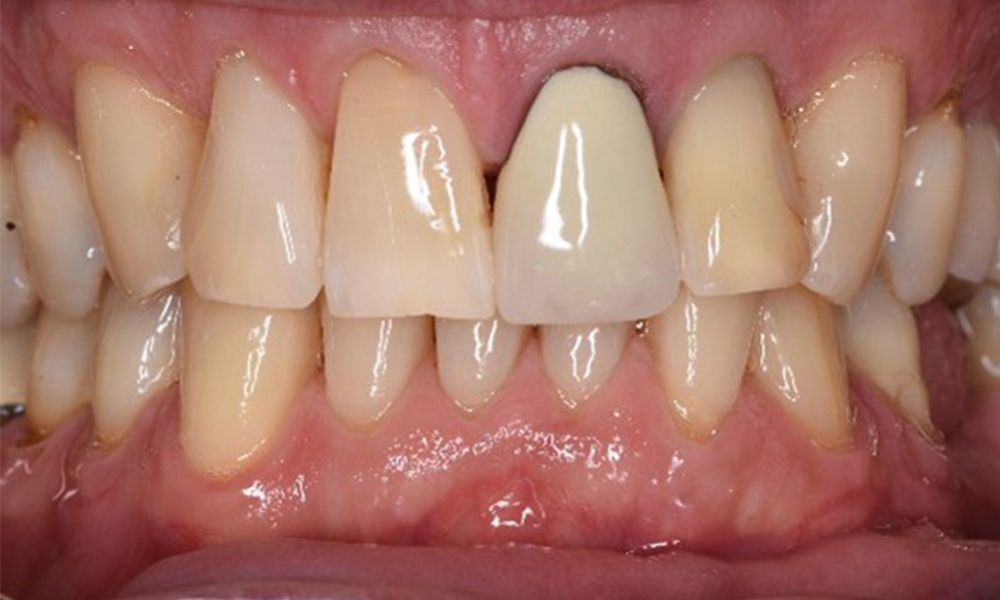

Patientenfälle nach IPCUm das Zusammenspiel der für den IPC definierten Bedarfs- und Risikofaktoren sowie die Auswirkungen einzelner Faktoren zu illustrieren, dienen nachstehende Fallbeispiele*. Die mundgesunde DiabetikerinEine 51-jährige mundgesunde Diabetikerin stellt sich zur Präventionssitzung vor. Die Blutzuckerwerte sind stabil bei einem HbA1c = 6,2%, folglich gilt sie mit dem entsprechenden Medikament Metformin (Antidiabetikum) als suffizient eingestellt. Die Patientin hat keine bestehenden Versorgungen oder orale Vorerkrankungen. Anhand der aktuellen Befunde lässt sich eine Gingivitis bei sonst stabilem parodontalem Zustand (Stage II, Grad B) feststellen. mehr Infos Fallpräsentation: Management komplexer ZahnprothetikEs ist längst bekannt, dass Mundgesundheit und Allgemeingesundheit in direktem Zusammenhang stehen und einen zum Teil bidirektionalen Einfluss aufeinander haben. Die Berücksichtigung beider Faktoren sind bei der Planung der oralen Prävention und Therapie der Patienten in der Zahnarztpraxis unabdingbar. Dabei ist oberstes Ziel, die Gesundheit und die Lebensqualität der Patienten sowohl aus zahnmedizinischer -und medizinischer Sicht zu erhalten. mehr Infos Der (mund)-gesunde Patient mit ImplantatenDer 55-jährige Patient gibt in der Anamnese an, keine Allgemeinerkrankungen zu haben und keine Medikamente einzunehmen. Die Lebensgewohnheiten des Patienten sind ebenfalls unauffällig. Der Patient hat einige zahnärztliche Restaurationen und zwei Implantate (2. und 4. Quadrant). Anhand der aktuellen Befunde lässt sich eine Gingivitis bei stabilem parodontalen Zustand am reduzierten Parodont (Stadium III, Grad A) feststellen. mehr Infos Der gesunde Patient mit parodontaler Vorerkrankung & PeriimplantitisEin 52-jähriger Patient stellt sich zur Präventionssitzung vor. Der Patient hat keine Allgemeinerkrankungen und nimmt keine Medikamente ein. Er hat verschiedene zahnärztliche Versorgungen und zudem zwei aktive kariöse Läsionen. Außerdem verfügt der Patient über vier Implantate (2., 3. und 4. Quadrant). Es zeigt sich eine parodontale Vorerkrankung (Stadium IV, Grad B). Derzeit herrschen stabile parodontale Verhältnisse, lediglich am Implantat regio 36 zeigen sich Sondierungstiefen (ST) von 5 mm. Zudem lässt sich eine Gingivitis feststellen. mehr Infos Der Diabetiker mit ParodontitisDieser Fallbericht eines 52-jährigen Mannes mit Typ-2-Diabetes und Parodontitis hebt hervor, wie durch individuelle Vorsorgemaßnahmen, die Gesundheit des Zahnhalteapparates erhalten bzw. das Fortschreiten der Erkrankung kontrolliert werden kann. mehr Infos Der 28-jährige Raucher mit ZahnerosionenDieser Fallbericht eines 28-jährigen Rauchers mit Zahnerosionen zeigt die Bedeutung personalisierter Patientenprofile. Er unterstreicht die Notwendigkeit, sowohl die Mundgesundheit als auch die allgemeine Gesundheit zu berücksichtigen, um Erkrankungen der Zähne bzw. des Zahnhalteapparates effektiv zu verhindern. mehr Infos Der Endokarditis-Patient mit aktiven KariesläsionenDer Patient ist 39 Jahre mit Z.n. Herzklappenersatz wegen Klappenfehlers und Endokarditis. Als Antikoagulans (Gerinnungshemmer) wird regelmäßig ASS 100 eingenommen. Aus dem Bereich Lebensstil ist die Ernährungsweise als kariesfördernd einzustufen, da mit hoher Regelmäßigkeit zuckerhaltige Lebensmittel sowie sechs bis sieben Mahlzeiten täglich verzehrt werden. Die Mundgesundheit des Patienten zeigt ein mittleres Kariesrisiko mit aktiven Läsionen. Das Parodontitisrisiko ist niedrig, es besteht eine Gingivitis. Es ergeben sich folgende Empfehlungen für die Prophylaxebehandlung. mehr Infos Die gesunde Patientin mit parodontaler VorerkrankungDie 68-jährige Patientin hat keine zahnmedizinisch relevanten allgemeingesundheitlichen Vorerkrankungen oder Medikation, auch aus dem Lebensstil ergibt sich kein besonderes Risiko. Die Patientin hat zwei Implantate (3. Quadrant, seit fünf Jahren) sowie eine parodontale Vorerkrankung (Parodontitis Stadium IV, Grad B) mit Zahnverlust. Derzeit zeigen sich stabile parodontale Verhältnisse. Für die Prophylaxesitzung ergeben sich vier Empfehlungen in den Bereichen Anamnese/Befund, Motivation/Instruktion, der Wahl der geeigneten Instrumente und für Resümee/Folgetermin. mehr Infos

NIWOP – No Implantology without PeriodontologyDer Transplantationspatient mit GingivawucherungenEin 71-jähriger Patient mit Z.n. Nierentransplantation und Hypertonie (Bluthochdruck) stellt sich vor. Bedingt durch die Krankengeschichte ist eine Dauermedikation mit Cyclosporin, zur Unterdrückung der Immunabwehr, und Amlodipin, zur Blutdrucksenkung, erforderlich. Außerdem berichtet der Patient über empfindliches Zahnfleisch und Zahnfleischbluten. Aus mundgesundheitlicher Sicht zeigt sich ein saniertes Gebiss mit acht fehlenden Zähnen, ausgeprägte Gingivawucherungen, eine Parodontitis Stadium II, Grad B mit aktiven Taschen und eine initiale Wurzelkaries an Zahn 22. In der Kariesrisikoabschätzung wird ein mittleres Kariesrisiko (API 60) festgestellt. Für die Prophylaxesitzung lassen sich folgende Behandlungsempfehlungen ableiten. mehr Infos * mit freundlicher Genehmigung von Dr. G. Schmalz und Prof. Dr. D. Ziebolz MSc. Download AreaProxeo Produkte